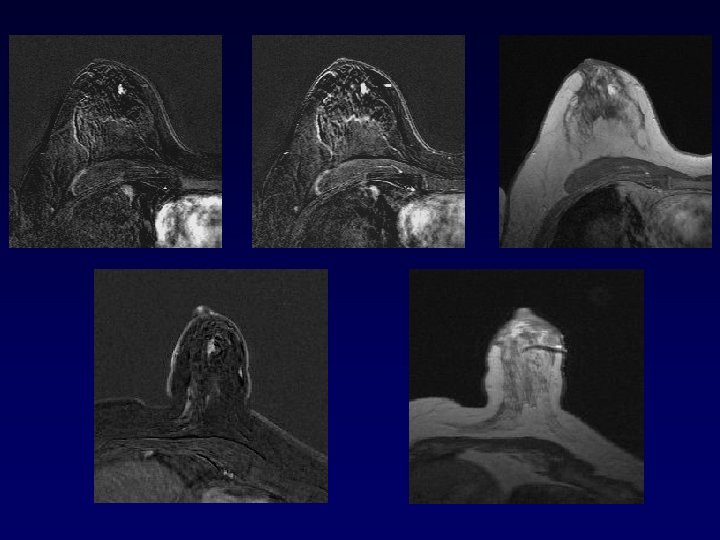

Angiogénèse dans CCIS haut grade

IRM et CCIS : la fin du consensus ? • Etude Lancet 2007 (C Kuhl) – 5960 patientes – Comparaison Mammographie/IRM – 167 diagnostic de CCIS – 89 CCIS de haut grade – Sen pour CCIS haut grade : • IRM = 98% • Mammographie = 52%